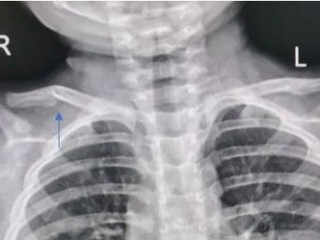

第一步,先搞清楚:锁骨骨折,一定是“轻伤”吗?

这还真不一定!咱们老百姓嘴里的“轻伤”和法律上的“轻伤”完全是两码事,法律上的伤情鉴定,那是非常严格和专业的,有专门的《人体损伤程度鉴定标准》,锁骨骨折,根据骨折的部位、程度(比如有没有移位、粉碎性骨折、有没有损伤到周围神经血管等),鉴定结果可能是“轻微伤”,也可能是“轻伤二级”或者“轻伤一级”,严重的甚至可能达到“重伤”。